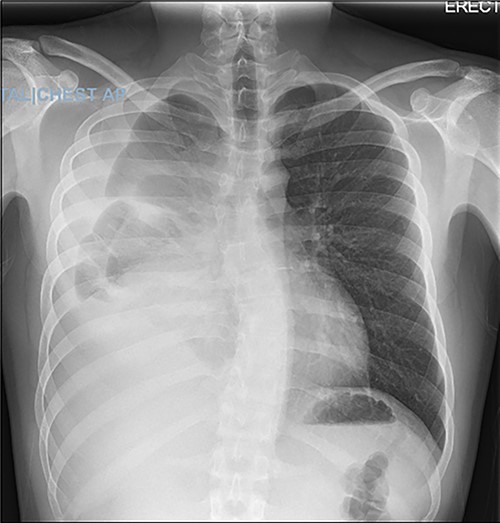

In the operating room, the patient was placed in the left lateral decubitus position exposing the right side of the chest. Upon entering the pleural cavity, a significant amount of bloody pleural fluid was seen. After fluid aspiration, the mediastinal mass was seen compressing the right lung (Fig. 3). Samples of the tumor were obtained and sent for frozen section analysis, which showed extensive necrosis and desmoplastic reaction, but no evidence of malignancy.

Intraoperative image with patient in left lateral decubitus position demonstrating the mass (black arrow) causing compression of the lung (white arrow).